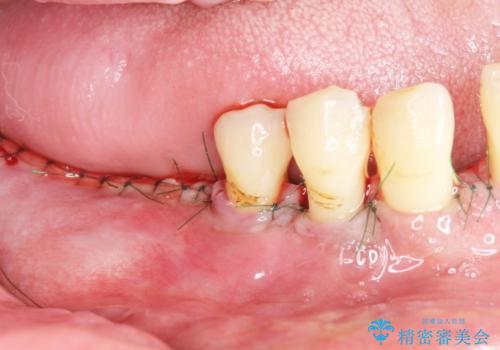

精査したところ、全顎的な重度の歯周病により右下の小臼歯(右下4)激しい動揺を認めました。

できるだけ自分の歯を残したいという患者様の強いご希望により、禁煙指導後再生療法(骨を増やす手術))を行いました。

再生療法から1年後リエントリー手術により骨の再生を確認し、骨外科処置(骨を平らにして歯周ポケットの根本的な改善を図る処置)を行ったのち、連結補綴を行いました。